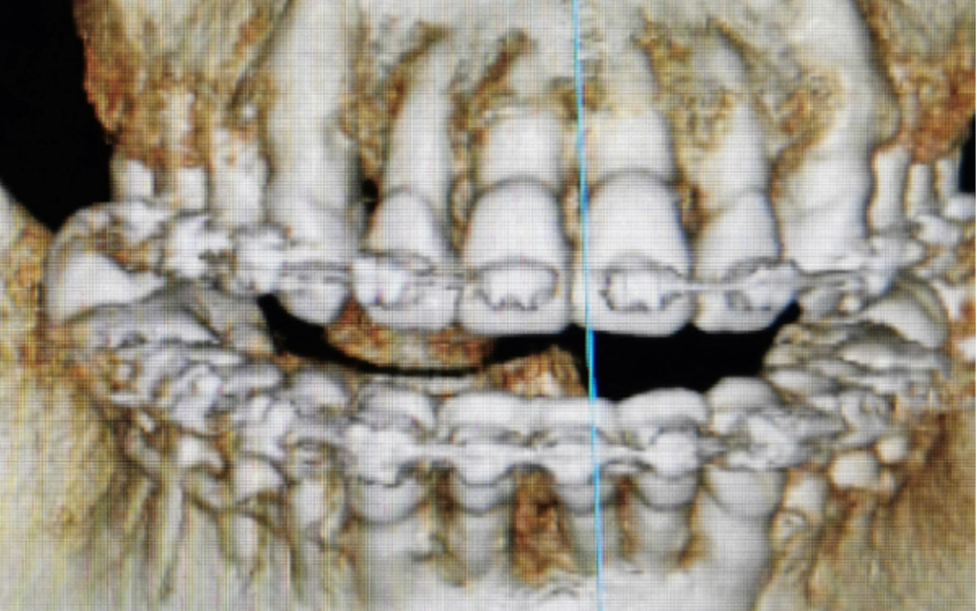

上前牙骨开窗一例

上前牙骨开窗一例